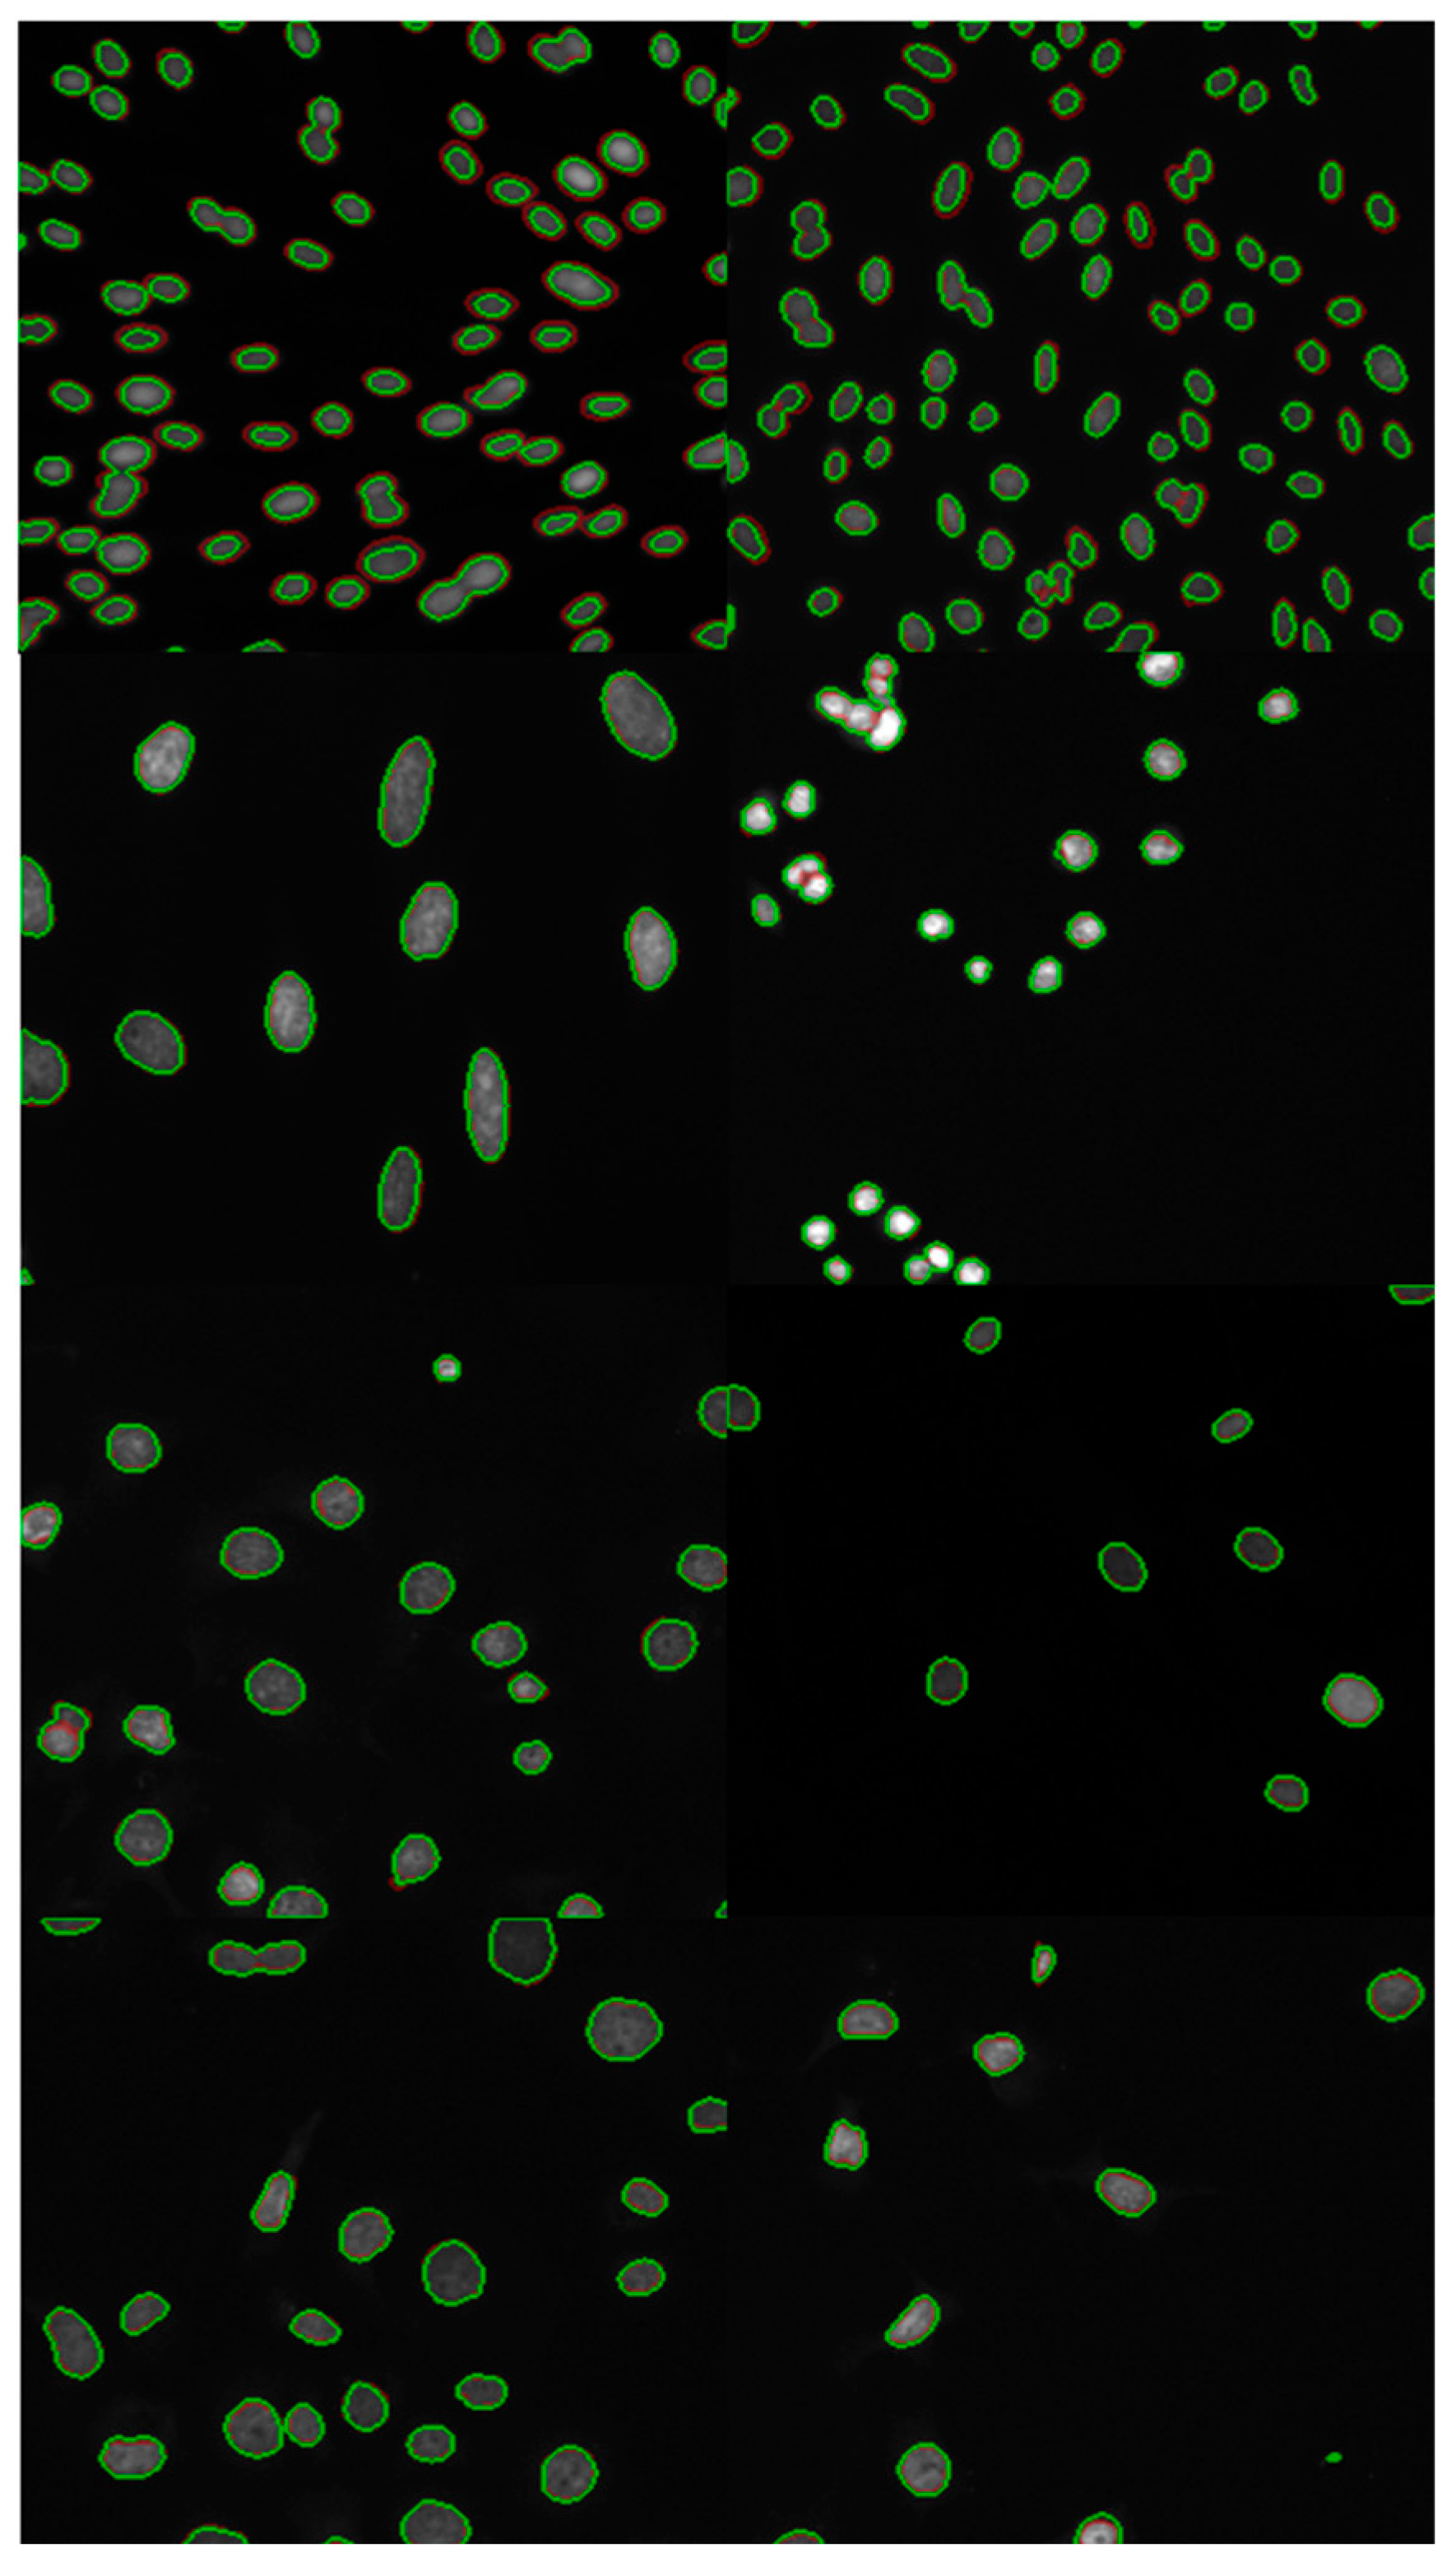

4.2.3. Visualize Segmentation Results

We selected some representative original images from the test set for visual analysis, which contain different size and density features, as shown in Figure 4. The green line represents the predicted value of the model, and the red line represents the label value. It can be seen that the predicted value basically overlaps with the label, and the model has achieved good prediction results. For further comparative evaluation of segmentation performance, Figure 5 presents a systematic visualization of polyp segmentation results across multiple state-of-the-art models (Unet, Unet++, SFA, PraNet) and our proposed method on challenging cases from both CVC-ColonDB and ETIS datasets. The ground-truth masks and model outputs are displayed in binary format, where our method demonstrates superior boundary adherence and completeness in capturing polyp morphology compared to baseline approaches, particularly for small and low-contrast lesions.

Figure 4. The green line represents the predicted value of the model, and the red line represents the label value.